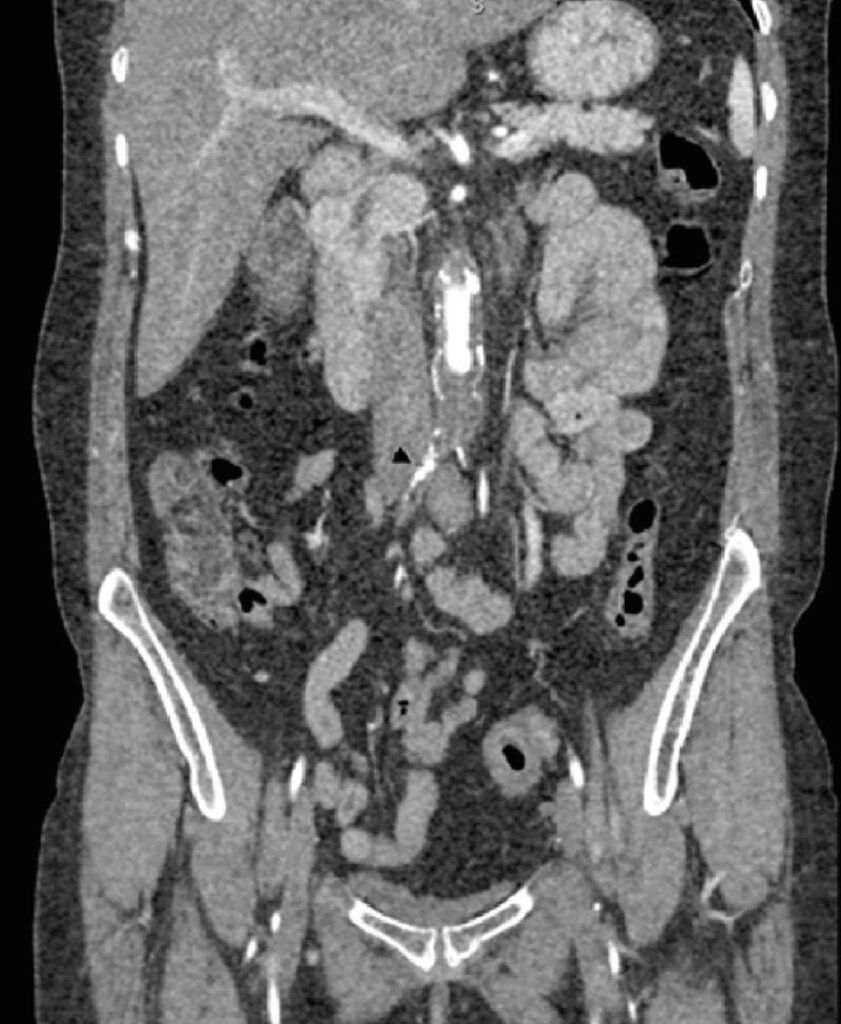

Mulher de 49 anos apresentou histórico progressivo de claudicação intermitente bilateral nas nádegas e panturrilha, atingindo uma distância de caminhada de 10 m. Era tabagista e tinha hipertensão. Não havia histórico de trombose venosa, edema de membros inferiores, veias varicosas nem sinais de doença venosa crônica. Ausência de pulsos femorais. A angiotomografia computadorizada evidenciou oclusão da aorta infra-renal com recanalização de ambas as artérias ilíacas. Curiosamente, a artéria ilíaca comum direita comprimia a veia ilíaca comum esquerda, que se encontrava aumentada ( ). Observavam-se colaterais pélvicos dilatados à esquerda: veias uterinas e veia gonadal ( ). Não havia compressão na veia renal esquerda.